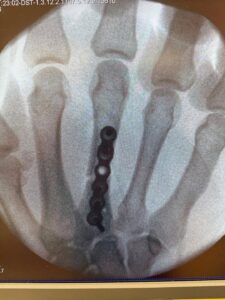

Tam tersine, yaşadığı sakatlığa rağmen soğukkanlılığını koruyarak oyunun kontrolünü eline aldı ve üç raundun sonunda hakemlerin oybirliğiyle galip gelen taraf oldu. Bu galibiyet, sadece teknik bir üstünlüğün değil, aynı zamanda güçlü bir iradenin de göstergesiydi. Maçın ardından Engizek, elini ilk raunda kırdığını fark ettiğini, ancak pes etmeyip maçı sonuna kadar sürdürdüğünü açıkladı.

Daha sonra yapılan kontrollerde kırığın ciddiyeti ortaya çıktı ve başarılı sporcu ameliyata alındı. Bu gelişme, Engizek’in hem savaşçı ruhunu hem de profesyonel duruşunu bir kez daha ortaya koydu. Zor koşullar altında dahi hedefinden şaşmayan, seyircisine daima mücadele azmini hissettiren Engizek, taraftarlarının gözünde bir kez daha gerçek bir şampiyon olduğunu ispatladı.